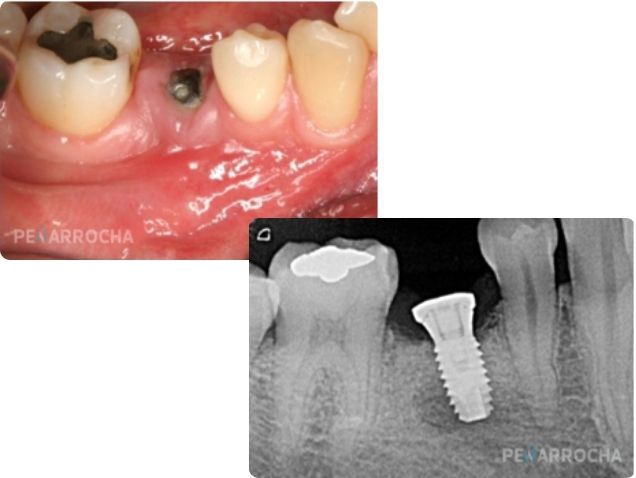

La periimplantitis apical es una infección aguda que afecta a la zona del ápice del implante, generalmente en las primeras semanas tras su colocación. Es una de las principales causas del fracaso temprano del implante y suele producirse por la presencia de restos contaminados en el lecho implantario, que son empujados hacia el extremo del implante durante su inserción.

Si el paciente experimenta dolor después de la colocación del implante, es fundamental sospechar de esta infección, aunque en fases iniciales puede no haber signos evidentes como inflamación o radiolucidez periapical en las radiografías.

Tratamiento:

• Realizar una intervención quirúrgica para limpiar la zona afectada y eliminar el tejido de granulación en el periápice del implante.

• Si el implante no presenta movilidad y la infección se trata a tiempo, el pronóstico es favorable.

Los Dres. Peñarrocha han sido pioneros en el diagnóstico y tratamiento de la periimplantitis apical. Su amplia experiencia en este campo los ha convertido en referentes en España y a nivel internacional.